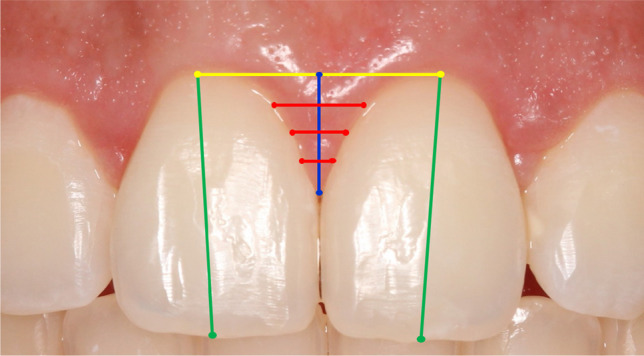

A photographic protocol was executed at baseline and follow-up periods by the same trained and calibrated examiner (C.A.S.A.) using a Canon professional camera, 100 mm macro lens, and circular flash. Patients were lying in a horizontal position, with a lip retractor, arches occluded, and the examiner took the pictures in a frontal view and parallel to the occlusal plane [9]. All the image files were transferred to the ImageJ software (National Institutes of Health, EUA, ImageJ version v1.51j8) where they were analyzed by one trained and calibrated examiner (M.U.M.). Measurements were done twice by the same examiner, with an interval of 15 days, and the average values of the two measurements were used for analysis. To calibrate the software regarding each image, the examiner drew a line from the most distal point of the right central incisor to the most distal point of the left central incisor. This line was then converted into millimeters considering the exact same clinical measurement. Image files of T0, T3, T6, and T12 were used to measure the following parameters (Fig. 1):

- Clinical crown length (CCL): a line was drawn starting on the tooth zenith and extending to the most central point of the incisal edge in CI, LI, and CN group of teeth.

Interdental Papilla height (PH): at first, a line was drawn from one zenith tooth to his adjacent zenith tooth. Then, a vertical line was drawn from the papilla point site to the horizontal line in three groups central papilla (CP), central-lateral papilla (CLP), and lateral-canine papilla (LCP).

Interdental Papilla width (PW): the PH line was divided into three equidistant horizontal lines being a superior, median, and an inferior line.

Fig. 1.

The variables collected were the clinical crown length (green), interdental papilla height (blue), and interdental papilla width subdivided into three equidistant fractions (red). For such measurements, the positions of the gingival zeniths (yellow) were used